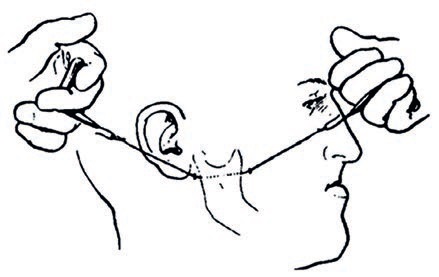

Aparat stały grubołukowy łuk językowy – zastosowanie i wykonawstwo laboratoryjne

TITLE: Fixed braces lingual arch – application and workmanship laboratory

Pierwsze próby prostowan...